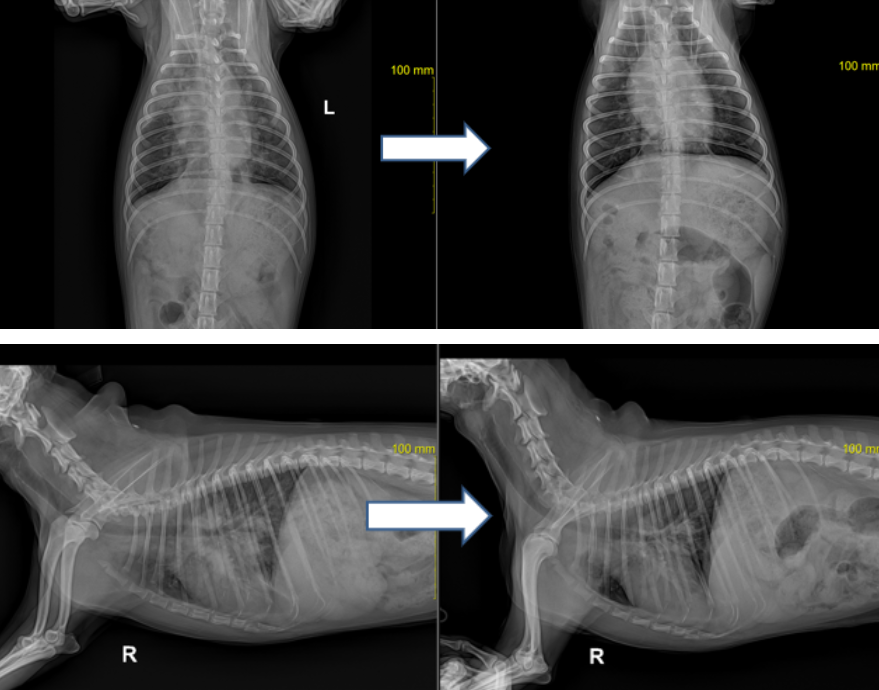

스테로이드와 항생제 그리고 수액처치 후 환자의 개선속도는 급격하게 좋아졌으며

기침 호흡곤란 증상도 매우 좋아졌습니다. (방사선은 치료 후 3일 경과 사진) ▼

현재도 지속적으로 스테로이드 치료를 하고 있으며 용량을 천천히 감량하면서 지켜보고 있습니다.

스테로이드 치료를 함에 따라 혈 중 호산구 수치도 눈에 띄게 낮아지는 것도 함께 확인되었습니다.